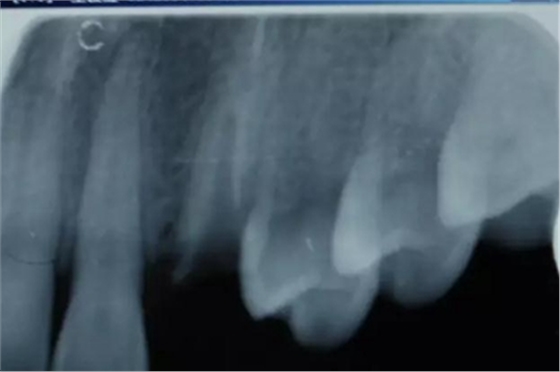

病例一 女性,20歲,大學(xué)生,要求補(bǔ)牙,檢查口內(nèi)可見A6大面積缺損,近中牙齦息肉,拍X片,根管充填物略差,但根周未見明顯陰影,口內(nèi)檢查無叩痛。建議患者冠延長手術(shù)+高嵌體修復(fù)。

患牙遠(yuǎn)中邊緣嵴完整,強(qiáng)度沒有降低,故擬保留遠(yuǎn)中邊緣嵴,高嵌體修復(fù)。首先去除腐質(zhì)及原墊底材料,流體樹脂+3M Z350XT樹脂墊底。局麻下行冠延長手術(shù)。在此需要提及個人的一個觀點(diǎn)。冠延長手術(shù)原則上要求3-6個月以上才能永久修復(fù)。但是個人喜歡后牙肩臺建立在齦上,所以修復(fù)后的修復(fù)體邊緣位于牙齦上方1mm,對牙周的愈合影響較小(如果為齦下邊緣則要慎重),故該患者術(shù)中按照齦上邊緣的設(shè)計(jì)進(jìn)行冠延長手術(shù)。以下為術(shù)中: